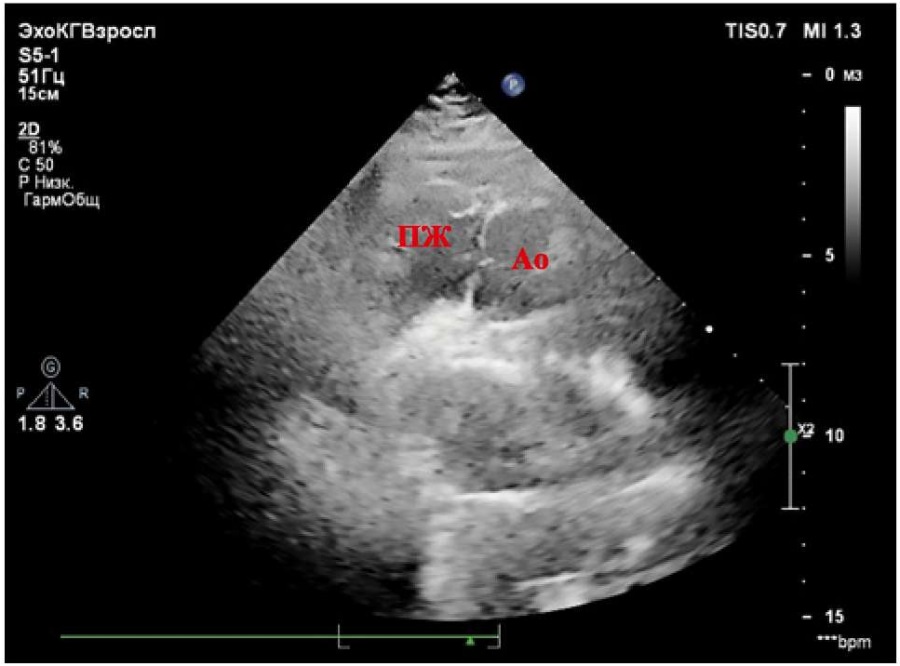

При проведении ЭхоКГ, представленной на рисунках 1–4, выявлено правосформированное леворасположенное сердце. Печень расположена в анатомически положенном месте (справа). Анатомически ПП (ориентир — заслонка полой вены) соединён с анатомически ЛЖ (анатомический ориентир — гладкая эндокардиальная поверхность), расположенным справа (дискордантное АВ-соединение). Диаметр ПП — 36×42 мм. Базальный диаметр ЛЖ из апикальной позиции (приточный отдел) — 38 мм, глобальная сократимость не снижена. Толщина боковой стенки ЛЖ — 7–8 мм. ПП соединяется с ЛЖ посредством двустворчатого (анатомически митрального) клапана, крепление створок которого расположено ниже крепления створок ТК. Митральная регургитация (+/++). От анатомически ЛЖ отходит ствол ЛА (несёт венозную кровь), с наличием митрально-легочного фиброзного продолжения. Диаметр ЛА на уровне клапана — 26 мм. Максимальный градиент на клапане ЛА — 8 мм рт. ст. Пульмональная регургитация (+). Визуализируются бифуркация и ветви ЛА, не расширены. Слева от ЛЖ располагается анатомически ПЖ (анатомический ориентир — модераторный пучок и трабекулярность). ПЖ соединяется с анатомически ЛП посредством анатомически ТК. Трикуспидальная регургитация (++/+++), створки утолщены. Сухожильные хорды ТК крепятся к перегородке и трабекулам ПЖ. Базальный диаметр ПЖ из апикальной позиции — 49 мм. Фракция изменения площади (ФИП) ПЖ — 40% (норма — более 35%) [7][8]. Систолическая экскурсия плоскости трикуспидального кольца в М-режиме (TAPSE) — 14,7 мм (норма — более 17 мм) [7][8]. Толщина боковой стенки ПЖ — 7–8 мм, МЖП — 9 мм. Диаметр ЛП — 46×68 мм. Объём ЛП — 80 мл. От анатомически ПЖ отходит Ао (несёт артериальную кровь). Диаметр корня Ао — 34 мм, восходящего отдела Ао — 29 мм, дуга Ао — 29 мм. Аортальный клапан (АК) двухстворчатый, регургитации нет. Максимальный градиент на АК — 8 мм рт. ст. Скорость кровотока в нисходящем отделе Ао в пределах нормы. Отсутствует контакт между артериальным (анатомически ТК) АВ-клапаном и магистральным сосудом (Ао), что свидетельствует об инверсионном положении сосудов. Ао расположена спереди и слева от ЛА. Патологические шунты через МПП и МЖП при цветовом картировании не регистрируются, смещения септальной створки ТК нет. Допплер: ЕТК — 108 см/сек., АТК — 32 см/сек., ебокТК — 19 см/сек., еМЖП — 11,7 см/сек., sТК — 8 см/сек. (норма для ТК — более 9,5 см/сек.) [7], что позволяет косвенно судить о наличии нарушения регионарной систолической функции ПЖ. ta-eТК — 625 мс, tsТК — 354 мс, Teim-индекс — 0,77 (норма — менее 0,54), что также косвенно указывает на наличие нарушения регионарной систолической функции ПЖ. Е/еТКср 7,5 — косвенный признак отсутствия высокого конечного диастолического давления в ПЖ [7][8].

Рисунок 3. Парастернальная позиция по длинной оси. Отхождение аорты от анатомически правого желудочка. Отсутствует митрально-аортальное соединение.

Примечание: ПЖ — правый желудочек, Ао — аорта.

Figure 3. Parasternal long axis view. Aorta originates from the anatomically right ventricle. There is no mitral-aortic junction.

Note: RV — right ventricle, Ao — aorta.